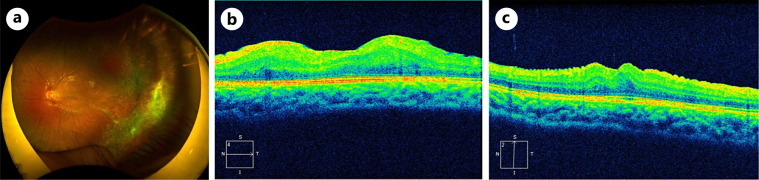

Case presentation: A 7-year-old girl presented with the chief complaint of decreased visual acuity in the left eye during a school examination. Fundus examination revealed retinal folds with FT extending from the peripheral retina to the posterior pole of the left eye. Despite interventions such as retinal photocoagulation and encircling buckling aimed at reducing the traction on the macula, OCT revealed persistent deep retinal folds and a thickened outer nuclear layer (ONL), indicating gradually increasing macular traction, which contributed to vision loss. A subsequent vitrectomy alleviated the macular traction, enhanced the retinal morphology, and reduced ONL thickening regardless of persistent ectopic inner foveal layers.

Conclusions: Macular morphological changes before and after vitrectomy in a pediatric case of FEVR can be observed using OCT. Vitrectomy with FT removal may be effective in partially improving macular morphology in FEVR with macular traction.